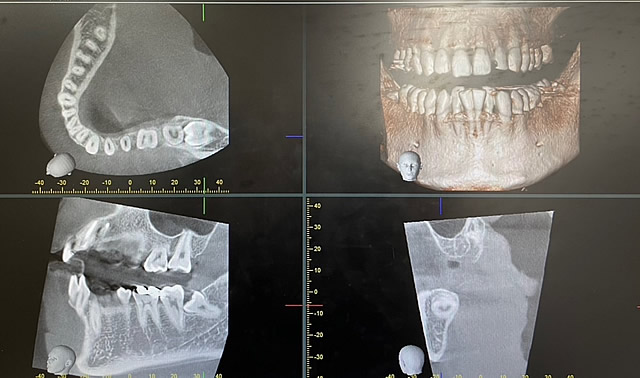

当院では、複雑な根管形態を可能な限り追従できるようにCT撮影も利用して、最小限の削合になるよう注意して治療しています。結論ですが、歯の性質は変わりません。治療の方針は、症状次第ですが神経を保存することが絶対ではなく、神経をとったとしても痛みがなく噛めることがその歯にとっての最善の治療のゴールかと思います。

悪い影響を与える恐れのある親知らずについては、ご相談・診断の後、当院で抜歯することができます。CTも完備していますので、親知らず抜歯の際に確認が必要な下顎管や上顎洞といった組織との位置関係も把握することができ、より安全に抜歯できます。(親知らずについては、身体的なご負担が少ないという理由で、お若いうちの抜歯をおすすめしています)